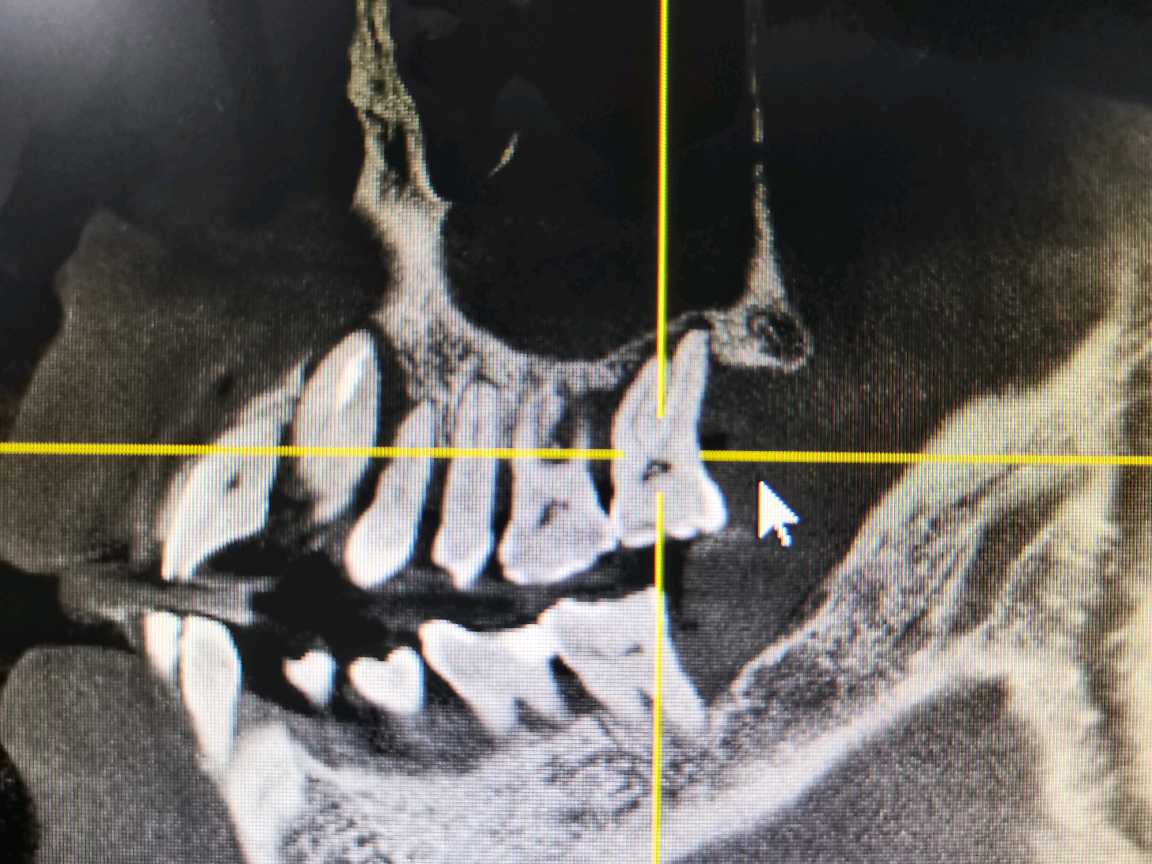

术前

试尖片